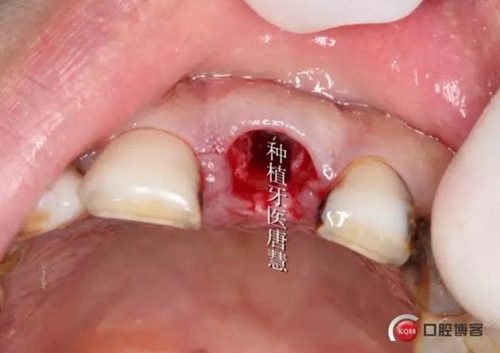

拔除患牙